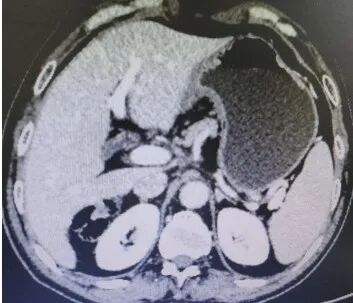

Abdominal CT films from August 13, 2019 (2 images)